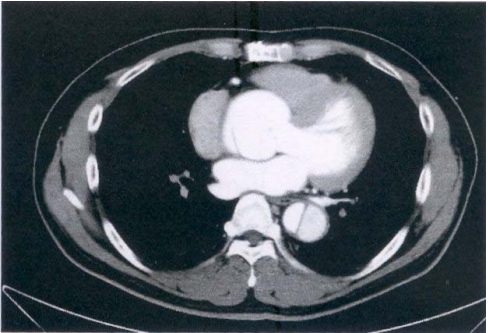

75 76 歲男性主訴胸悶及呼吸困難,注射對比劑後 CT 影像如附圖,則最可能的診斷為下列何者?

(A)主動脈剝離 (B)食道癌 (C)主動脈瓣狹窄 (D)左心房黏液瘤(Left atrial myxoma)